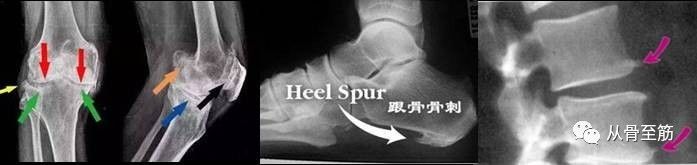

? ? ?一些在特殊的部位骨质增生,到一定程度后确实引起的疼痛、活动受限等临床症状,给我们带来了痛苦,此时称之为骨质增生症。在脊柱前方且增生较大者有时会对脊柱前方的食管、血管、神经等组织造成压迫引起临床症状;在后方者可能会压迫脊髓、神经根等引起临床症状;在关节内者可能会造成关节疼痛、活动受限等,特别是以膝关节骨质增生多见;跟骨骨质增生即跟骨骨刺有时会严重影响了患者正常生活。骨质增生症是病,得治。